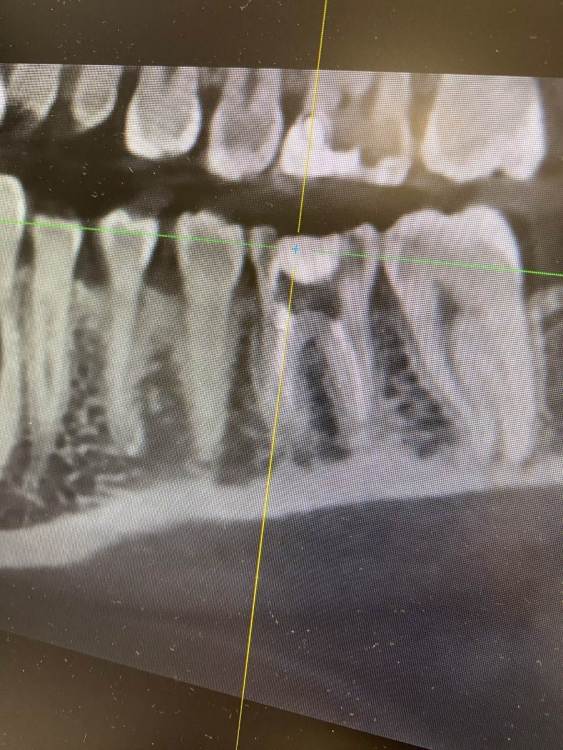

Нижняя шестерка. Удаляли нервы 4 года назад. Месяц назад заболел зуб(больно было давить на него)и кушать что то твердое.

пошла к стоматологу(сделала прицельный снимок,сказала периодонтит)

Вскрыла пломбу,распломбировала каналы.почистила, положила лекарство. Зуб

Все равно болел.

пришла во второй раз, поменяли лекарство,та же картина. Я сделала кт. Врач сказала на снимке киста. Положила лекарство. Не помогает. Подскажите что делать с таким зубом???

2E3177F8-AC20-4473-95F5-F378DAFD6547.jpeg

На зубе на самом деле "киста"

я бы советовал лечение, второй вариант, если не получится - удаление